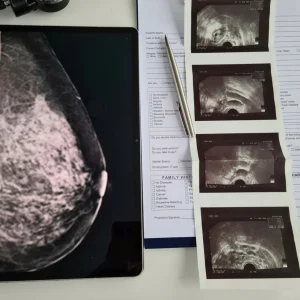

A recent study published in the Journal of the National Cancer Institute found that living in an area with high levels of particulate air pollution was associated with an increased incidence of breast cancer.

The most significant rises in breast cancer incidence occurred among women who, on average, lived in areas with higher particulate matter levels (PM2.5) in close proximity to their homes prior to their enrollment in the study. This contrasted those who lived in areas with lower levels of PM2.5.

The study revealed an 8% rise in breast cancer incidence among individuals residing in regions with higher exposure to PM2.5. While this increase may appear relatively modest, these findings hold significant importance, as air pollution is a widespread exposure that affects nearly everyone.

To examine how the association between air pollution and breast cancer might differ depending on the type of tumor, the researchers conducted separate evaluations for estrogen receptor-positive (ER+) and estrogen receptor-negative (ER-) tumors. They found that PM2.5 was associated with a higher incidence of ER+ breast cancer, but not ER-, tumors. This suggests that PM2.5 could potentially affect breast cancer development through an underlying biological mechanism related to endocrine disruption.